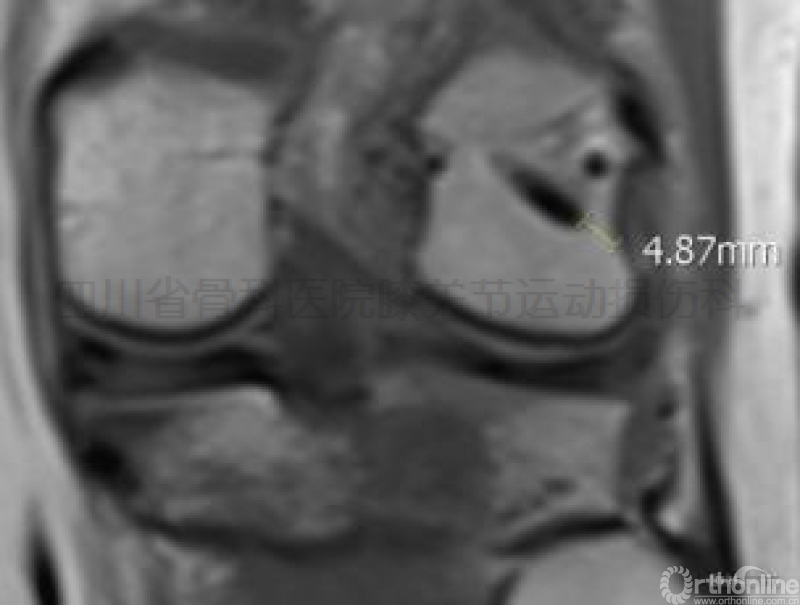

击入点与内侧副韧带股骨止点的最短距离大于25mm(图示五);

图示五经前内入口安全区逆向横穿于股骨内髁击入区所见:a、b点为RigidFix

鞘管击入点,c点为内侧副韧带股骨止点。击入点与该韧带之最短距离>25mm。